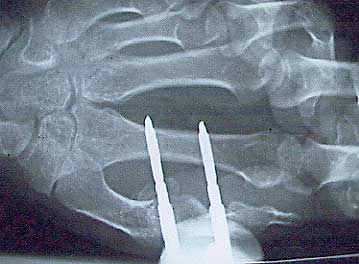

Hand. Bruch, Juli. Bis Dezember. Überstanden.